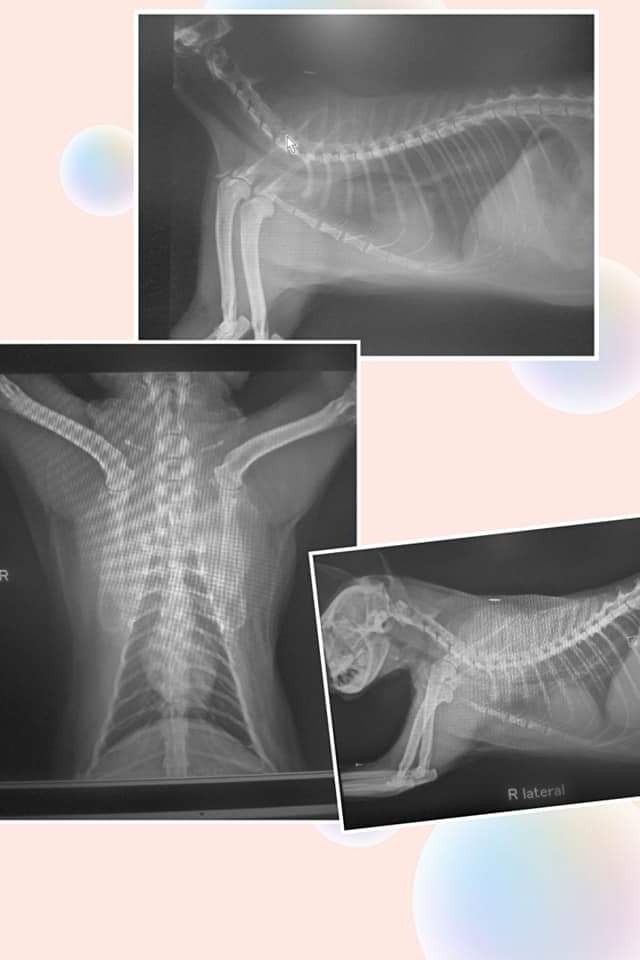

主題: 車禍吐血的貓咪 申請者姓名: 陳梅香 花色: 申請日期: 2020-01-19 17:20:46 申請者部落格: 申請者臉書網址: 所在縣市/合作醫院: 高雄市/樂生動物醫院 治療費用: 17250元 需求人數: 40人 已結案 (2024-05-31 18:22:21) 報名人員: Carrie(已付款)、Maggie(已付款)、lin789 x20(已付款)、Pon x2(已付款)、whobear、老虎狗讀者們 x15(已付款)、林小蝦(已付款)、 候補人員: 動物病情說明: 喵喵是在12月26日發現車禍吐血的街貓,目前在高雄樂生醫院治療中,27日入院時進食有困難,到31日可以吃罐頭,原先打算再没吃東西,醫生就施行插鼻胃管,因情況好轉所以作罷。但是肝指數很高,醫生解釋因為車禍遭撞擊而引起的,有針對定方面投藥,要等下次驗血才能知道是否降下來没?

有再抽血檢查,肝指數仍偏高,目前血紅素正常,表示出血應該止住了。

口腔內有小傷口潰爛,下顎部份應該是車禍造成的撞擊,有小斯裂傷。目前要觀察肝指數,是否有恢復正常值。

喵喵後來血檢肝指數已降為正常,沒有出血,紅血球也確定有回升,目前已經出院,謝謝協會和樂生的幫忙,喵喵得以重生。

8.點滴 300*12=3600 9.降腦壓藥物 ( 12/27~12/31) 800* 5=4000 10.鎮定 300 11.X光400*2=800